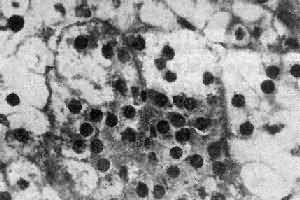

肾上腺皮质腺瘤与局灶性结节性增生的病变相似,两者可以并发。腺瘤通常是单侧单发性,并有薄层包膜,对周围组织有压迫现象,为鉴别的主要点。大小直径为1~5cm,切面黄色,有时呈红褐色,镜下多为类似束状带的泡沫状透明细胞,含有丰富类脂质,有时由类脂含量少的嗜酸性细胞构成,或者两种细胞混合存在。瘤细胞排列成团,由含有毛细血管的少量间质分隔(图15-16)。部分腺瘤为功能性,可引起醛固酮增多症或Cushing综合征,在形态上与非功能性腺瘤没有区别。

图15-16 肾上腺皮质腺瘤

上图 下图